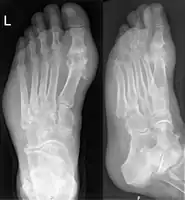

Gout may be diagnosed and treated without further investigations in someone with hyperuricemia and the classic acute arthritis of the base of the great toe (known as podagra). Synovial fluid analysis should be done if the diagnosis is in doubt.[15][45] Plain X-rays are usually normal and are not useful for confirming a diagnosis of early gout.[8] They may show signs of chronic gout such as bone erosion.[41]

Gout on X-rays of a left foot in the metatarsal-phalangeal joint of the big toe. Note also the soft tissue swelling at the lateral border of the foot.